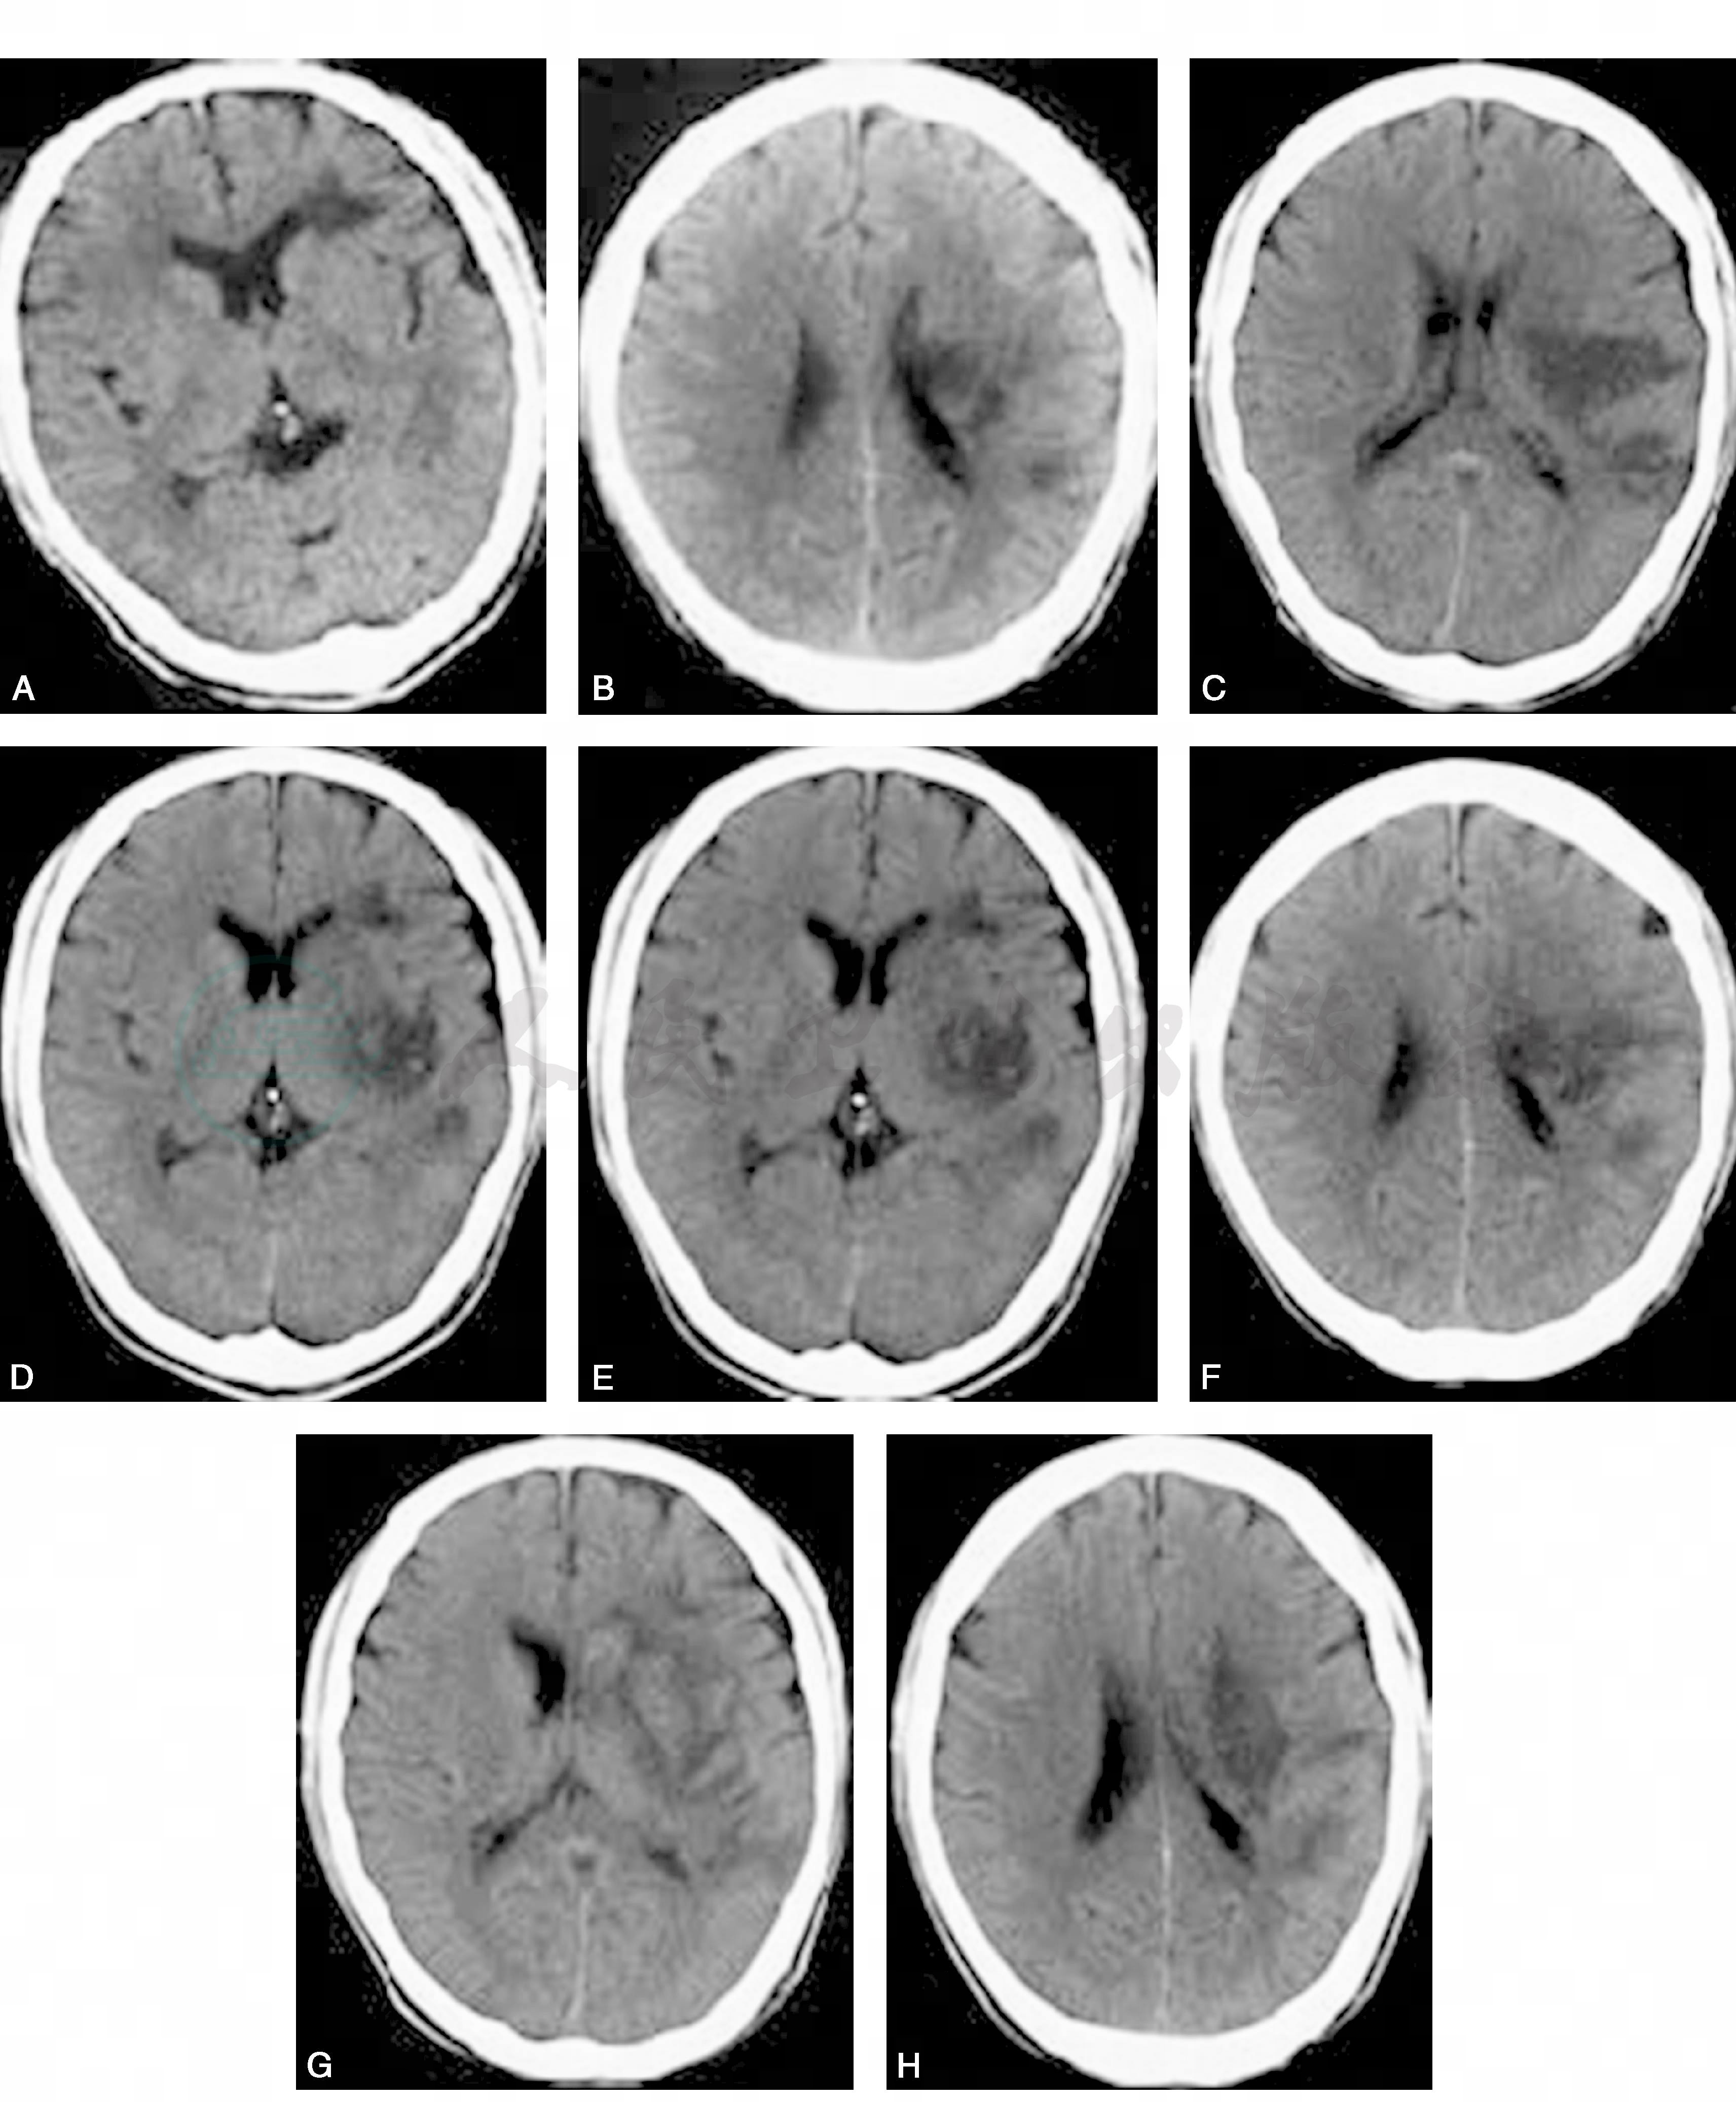

图1 外伤性颈动脉血栓栓塞性脑梗死患者颅脑CT表现

A.发病后1.5小时示左侧侧脑室前角外侧软化灶;B~D.发病后1日示左侧纹状体、侧脑室体旁和皮层多发梗死灶;E、F.发病后4日示左侧大脑中动脉分布区梗死灶较前增多;G、H.发病后10日示左侧大脑中动脉分布区梗死灶融合成片

患者男,68岁,因“突发右侧肢体活动不灵伴言语不清2小时”于2008年12月7日收入我院神经内科。起病前2小时有反复扛重物史。既往无高血压、糖尿病及冠状动脉粥样硬化性心脏病史。查体:血压120/80mmHg,颈总动脉、椎动脉、锁骨下动脉听诊区未闻及杂音。右侧中枢性面、舌瘫,右侧上下肢肌力3级,左侧5级。右侧足趾反射中性,左侧足趾反射阳性。窦性心律,心率55次/分,心电图无缺血改变。发病后1.5小时颅脑CT示左侧侧脑室前角外侧陈旧性软化灶(图1)。诊断为脑梗死,给予口服阿司匹林100mg/d,阿托伐他汀20mg/d,葛根素0.6g/d静滴等治疗,病情平稳无加重。发病后次日颅脑CT示左侧纹状体、侧脑室体旁和皮层多发梗死灶(图1),考虑栓子脱落所致,给予达肝素钠(法安明)5000U/d皮下注射,病情同入院时比较无明显变化。发病后第4天病情突然加重,呈嗜睡状态,完全性失语,右侧上下肢肌力0级,复查颅脑CT示左侧大脑中动脉(left middle cerebral artery,LMCA)分布区梗死灶较前增多(图1),考虑为栓子继续脱落所致。为了明确栓子来源,发病后第4天做颈部血管彩超显示左侧颈内动脉开口处有一随血流搏动、被冲击欲坠落的稍低回声影像,超声诊断为新鲜血凝块(图2)。发病后第5天做颈部血管彩超显示左侧颈内动脉开口处漂浮的血凝块全部消失,血凝块全部脱落。继续给予法安明抗凝,加用适量甘露醇脱水、依达拉奉注射液清除自由基等治疗,发病后第10天颅脑CT示LMCA分布区梗死灶融合成片(图1)。发病后第23天行头颈部CTA未见颅内外血管狭窄及斑块(图3)。患者经治疗后病情逐渐平稳出院。